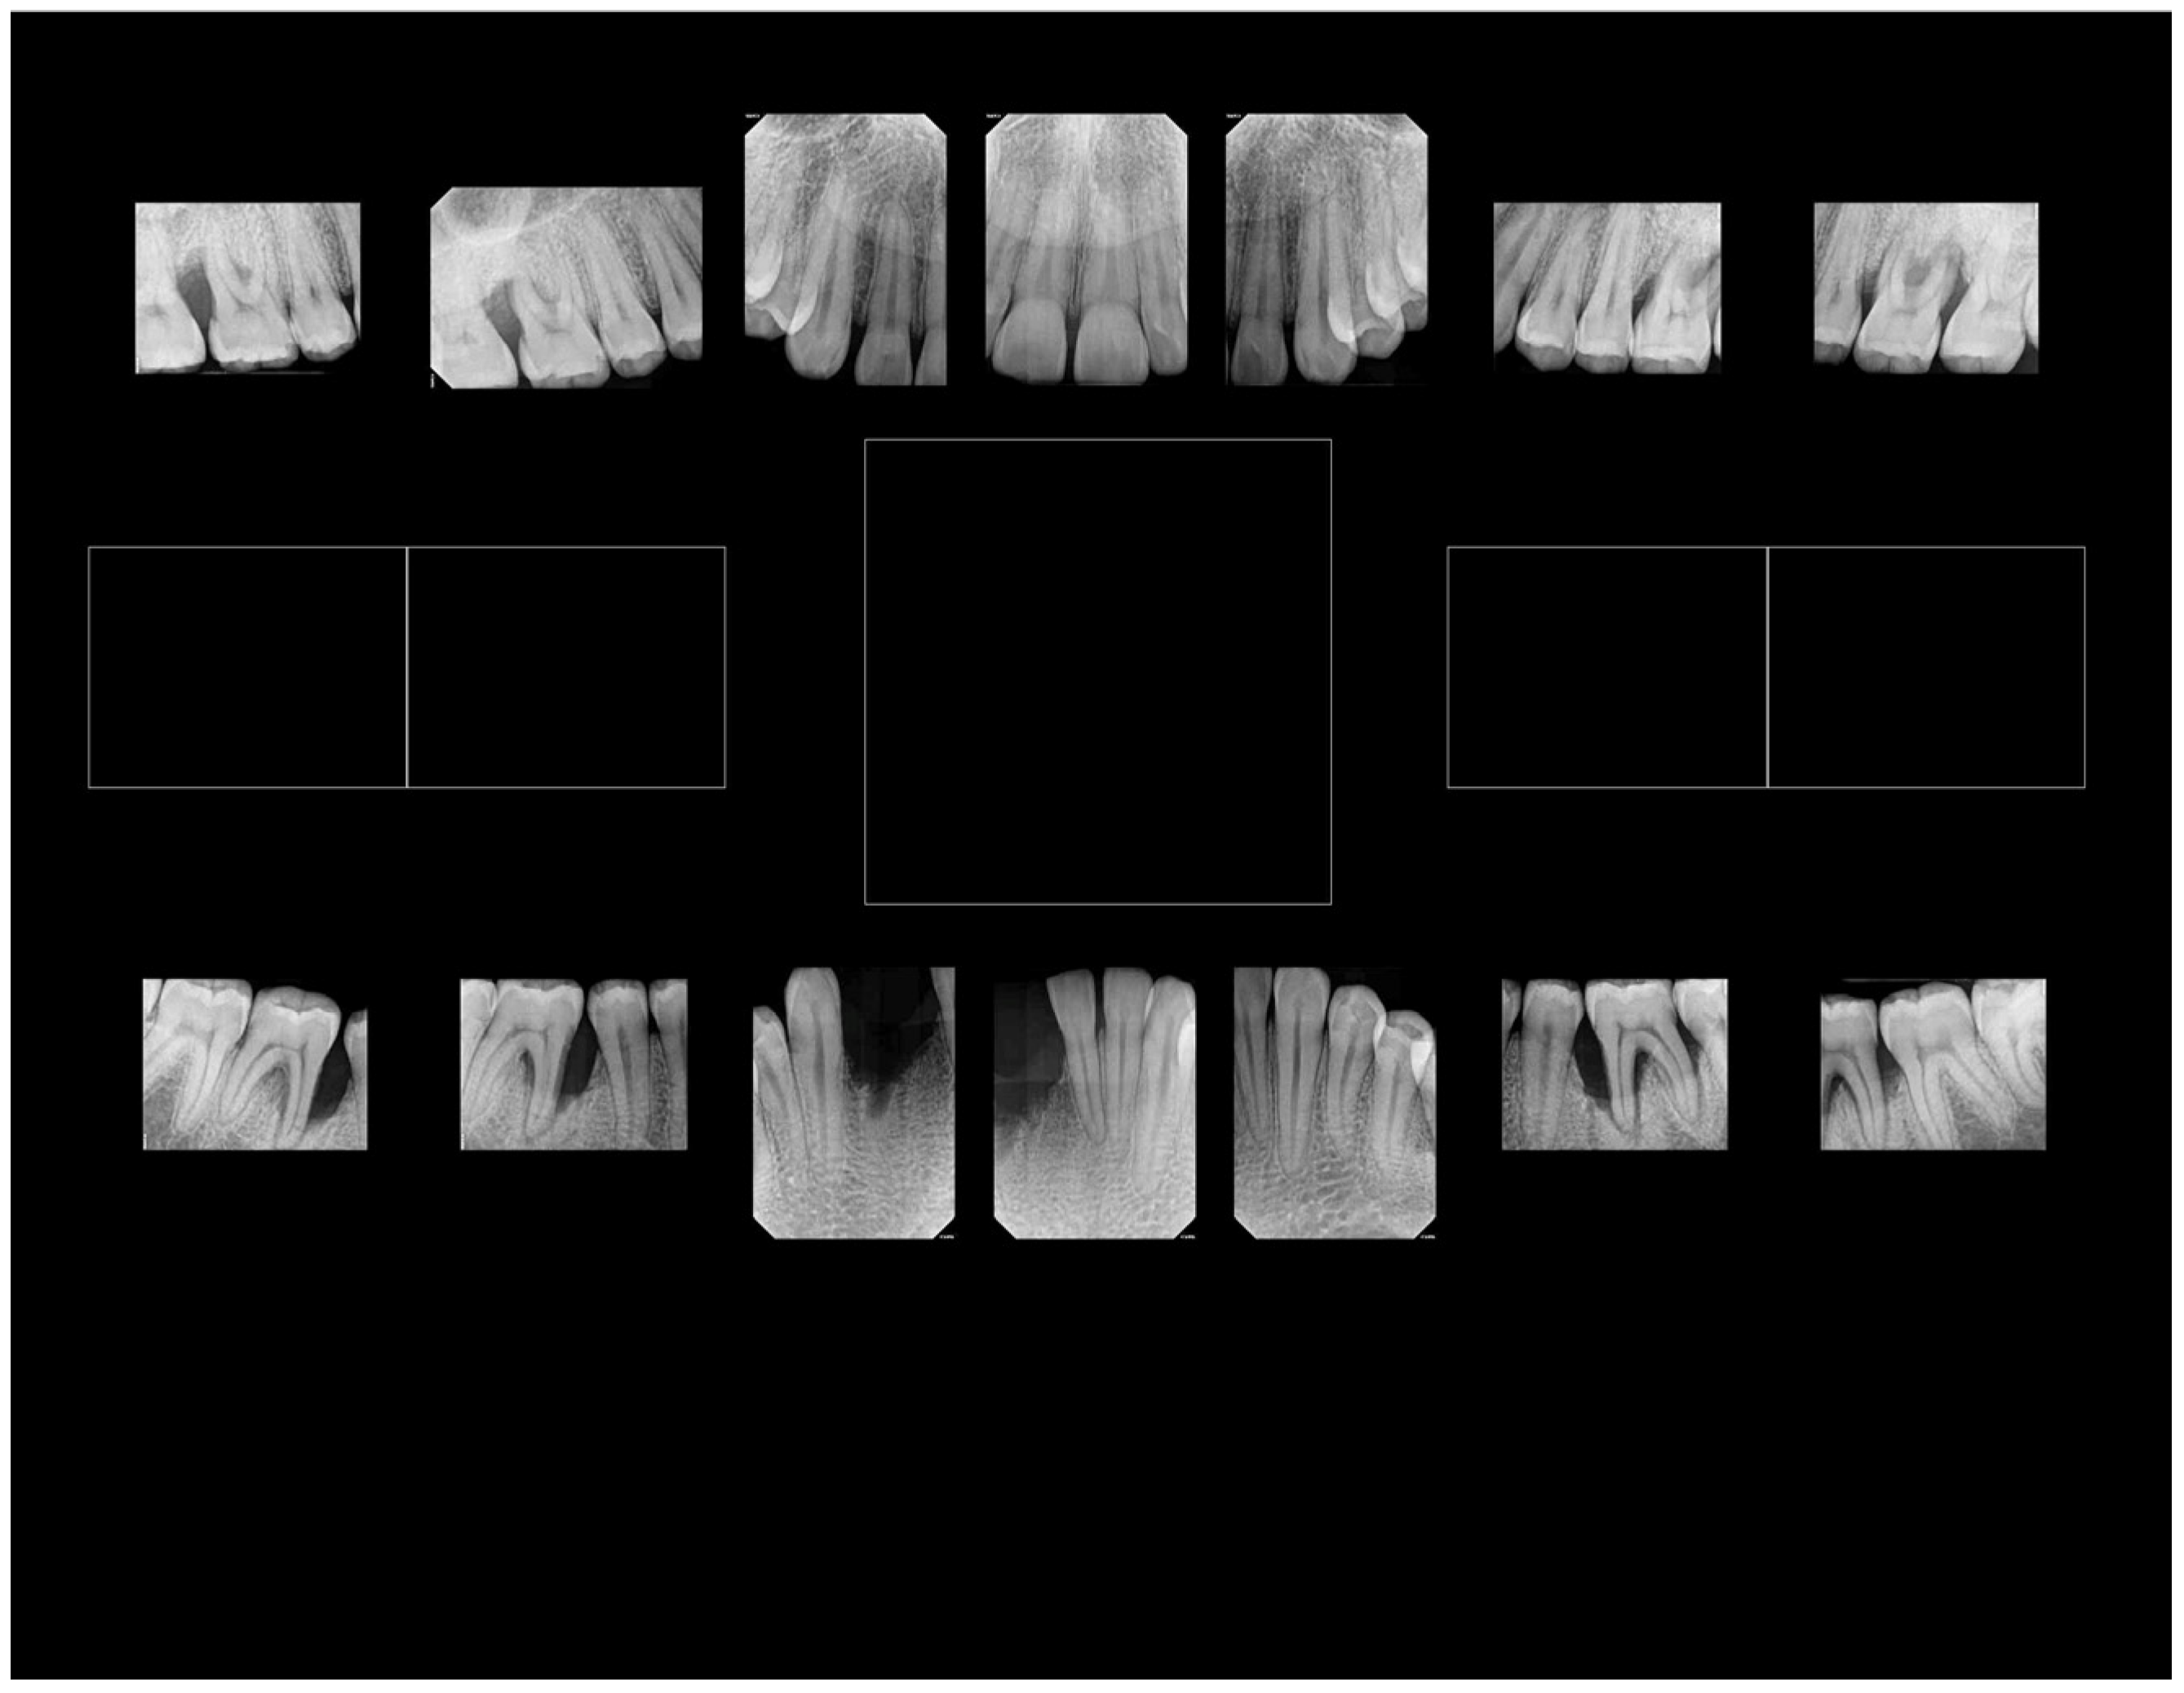

6. Distinct Characteristics of LAgP and an Alternative Approach for Assessing Treatment Success

- Distinct Characteristics of LAgP: An Illustrative Case.